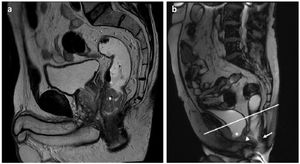

Other protocolsFor locoregional staging of rectal cancer, pelvic floor studies and defaecography, a 70–100 ml enema of ultrasound gel or warm saline solution is administered manually with a wide cone syringe. The sagittal plane is very useful in rectal studies (Fig. 7a and b). T1-weighted, T2-weighted and diffusion-weighted morphological sequences are usually used. To study the dynamics of the pelvic floor, SSFP “cine” sequences identical to those of the MRE are obtained, but in the sagittal plane. IV contrast is not routinely administered.

Pelvic MRI images with T2-weighted sequences in the sagittal plane after rectal administration of ultrasound gel (biphasic contrast). a) Cancer of the lower rectum (asterisk). b) Weakness of the pelvic floor with cystocele (asterisk), peritoneocele (arrowhead) and rectocele (arrow).

PCL: pubococcygeal line.